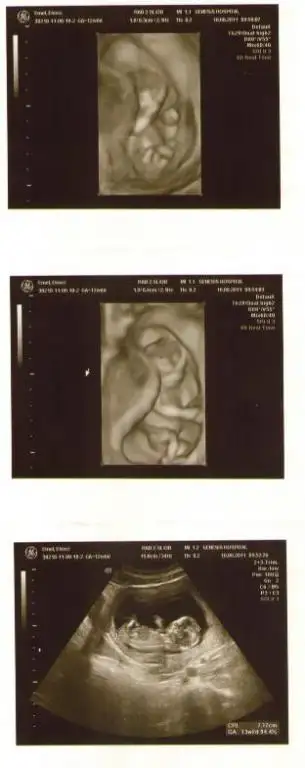

Kızlar merhaba, benide alın aranıza bakalım. 14 haftalık bebişim var inşallah. Doktor ultrasonda kıza benzetti ama bir dahaki kontrolümde netlik kazanırmış kısmetse. :69:

Buda bebeğimin ilk belli olan ultrason fotoğrafı :nazar: